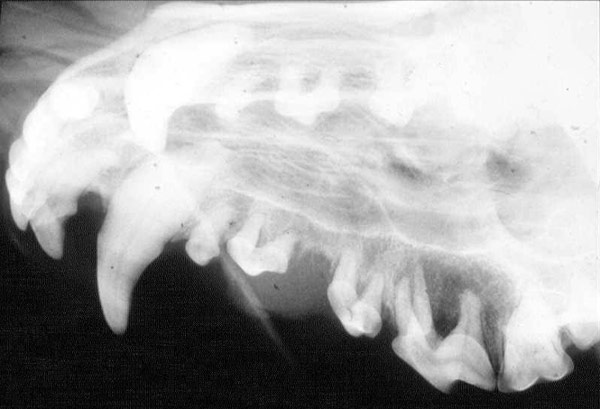

Extra oral 45 degree view of a maxilla

Extra oral 45 degree view of a maxilla. Dog had a Fibrosarcoma in the region of the upper right carnassial (108)